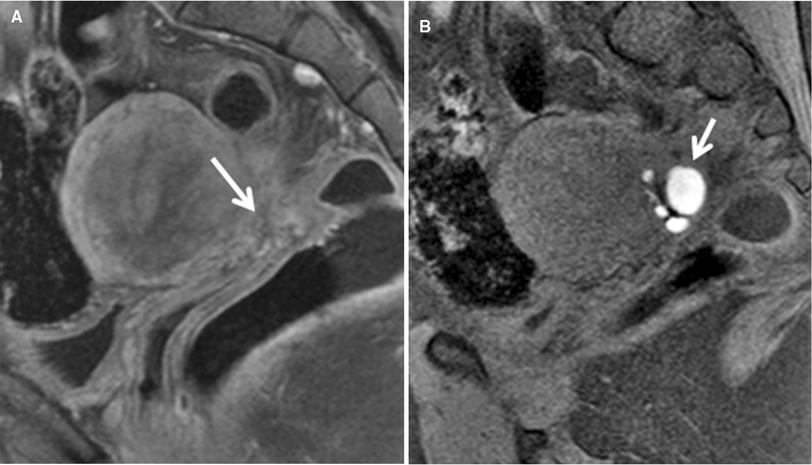

Sagittal T2WI of posterior cul-de-sac obliteration with retroflexion of the uterus in two patients. (a) Patient 1 with adhesions and fibrosis, which is evident as low T2 signal bands between the uterine serosa and rectum (white arrows). Retroflexion of the uterus is also identified (orange arrow).